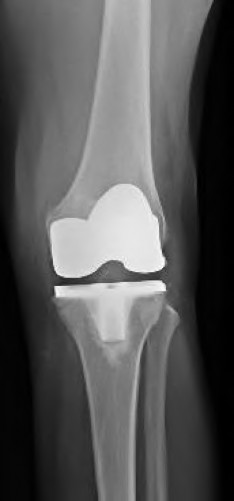

A 72-year-old female presents with progressive left thigh and knee pain for the last year. 5 years ago she sustained a femoral neck fracture treated with the implant seen in Figures A-C (current radiographs). The thigh pain is worse with weight-bearing. C-reactive

protein and erythrocyte sedimentation levels are within defined limits. Which of the following is the most likely cause of her pain?